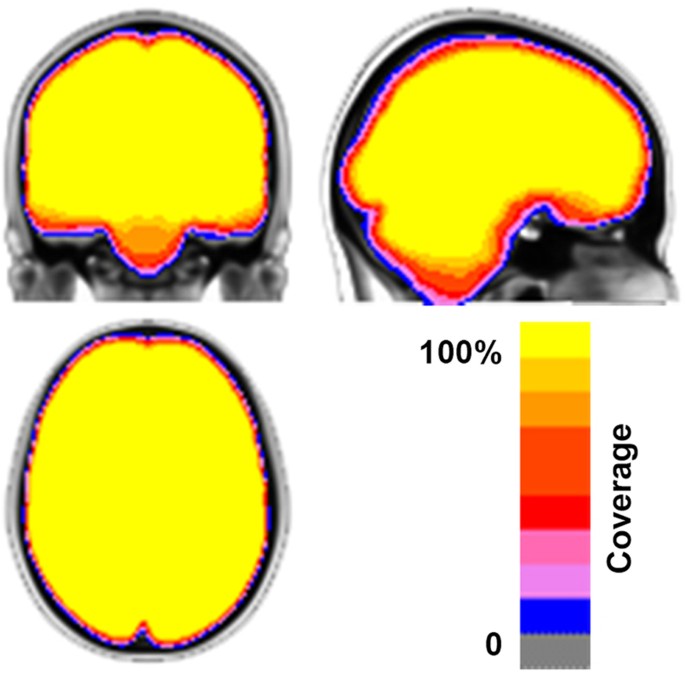

Consistent with the established FCP/INDI policy, all data contributed to CoRR was made available to users regardless of data quality. Justifications for this decision include the lack of consensus within the functional imaging community on criteria for quality assurance, and the utility of ‘lower quality’ datasets for facilitating the development of artifact correction techniques. For CoRR, the inclusion of datasets with significant artifacts related to factors such as motion are particularly valuable, as it enables the determination of the impact of such real-world confounds on reliability and reproducibility21,22. However, the absence of screening for data quality in the data release does not mean that the inclusion of poor quality datasets in imaging analyses is routine practice for the contributing sites. Figure 1 provides a summary map describing the anatomical coverage for rfMRI scans included in the CoRR dataset.